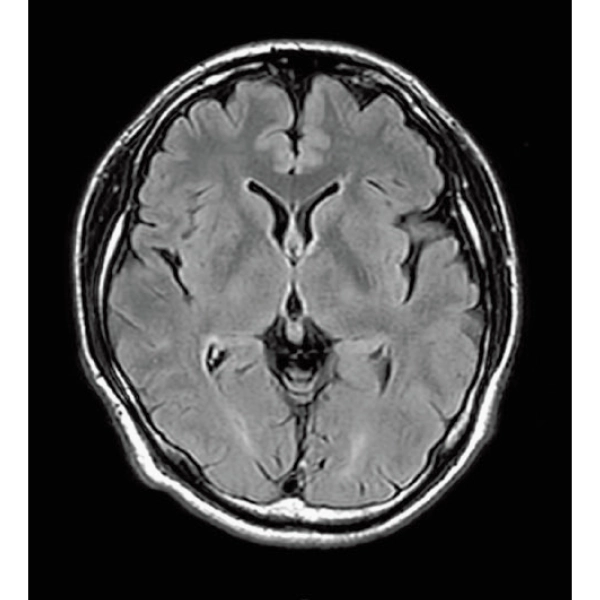

ShortScan

FLAIR, 1:14